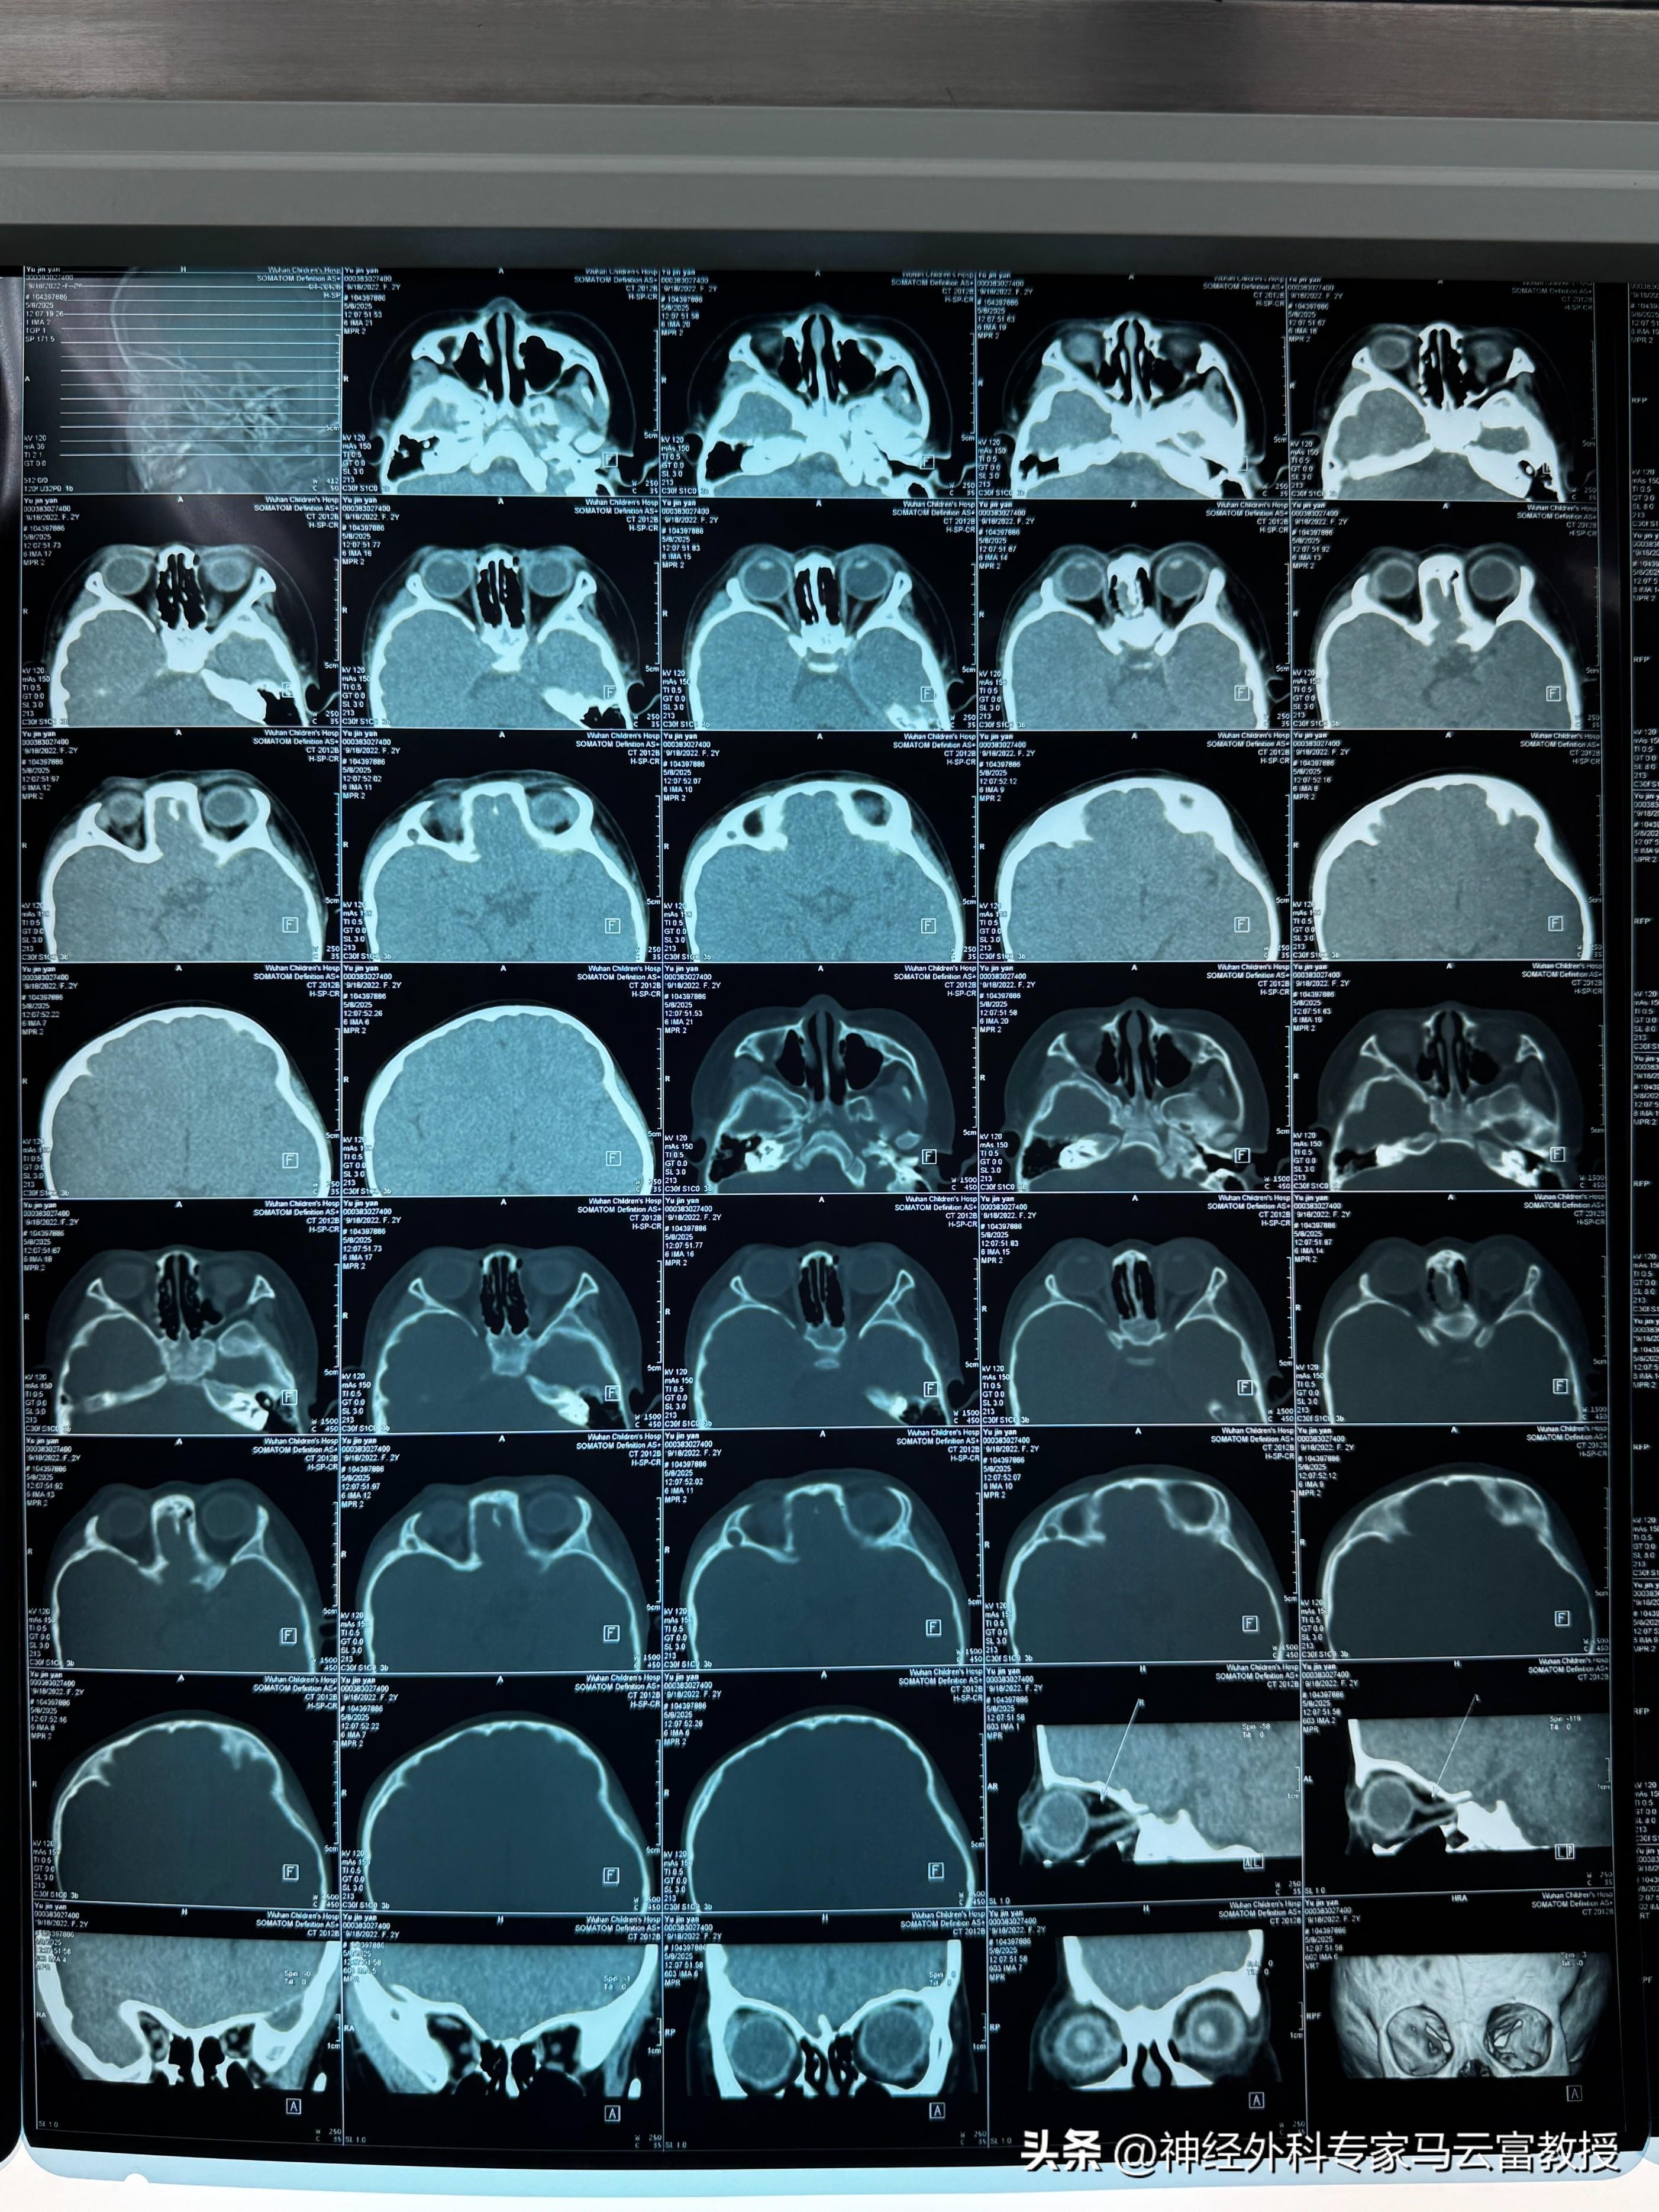

患兒術前顱腦CT

接診後,馬雲富教授高度重視,立即聯合夏星副主任組成專項診療團隊。考慮到患兒年齡小、顱骨結構特殊,且需同時解決顱縫早閉與眼眶骨畸形問題,團隊進行了多輪病例研討。爲實現精準矯治,團隊提前利用先進技術爲小魚進行顱腦內骨塊三維重建與個性化設計,反覆模擬手術流程,力求在矯正顱縫早閉的同時,最大程度修復右側眼眶骨畸形,還原顱骨與眼眶的正常生理形態。